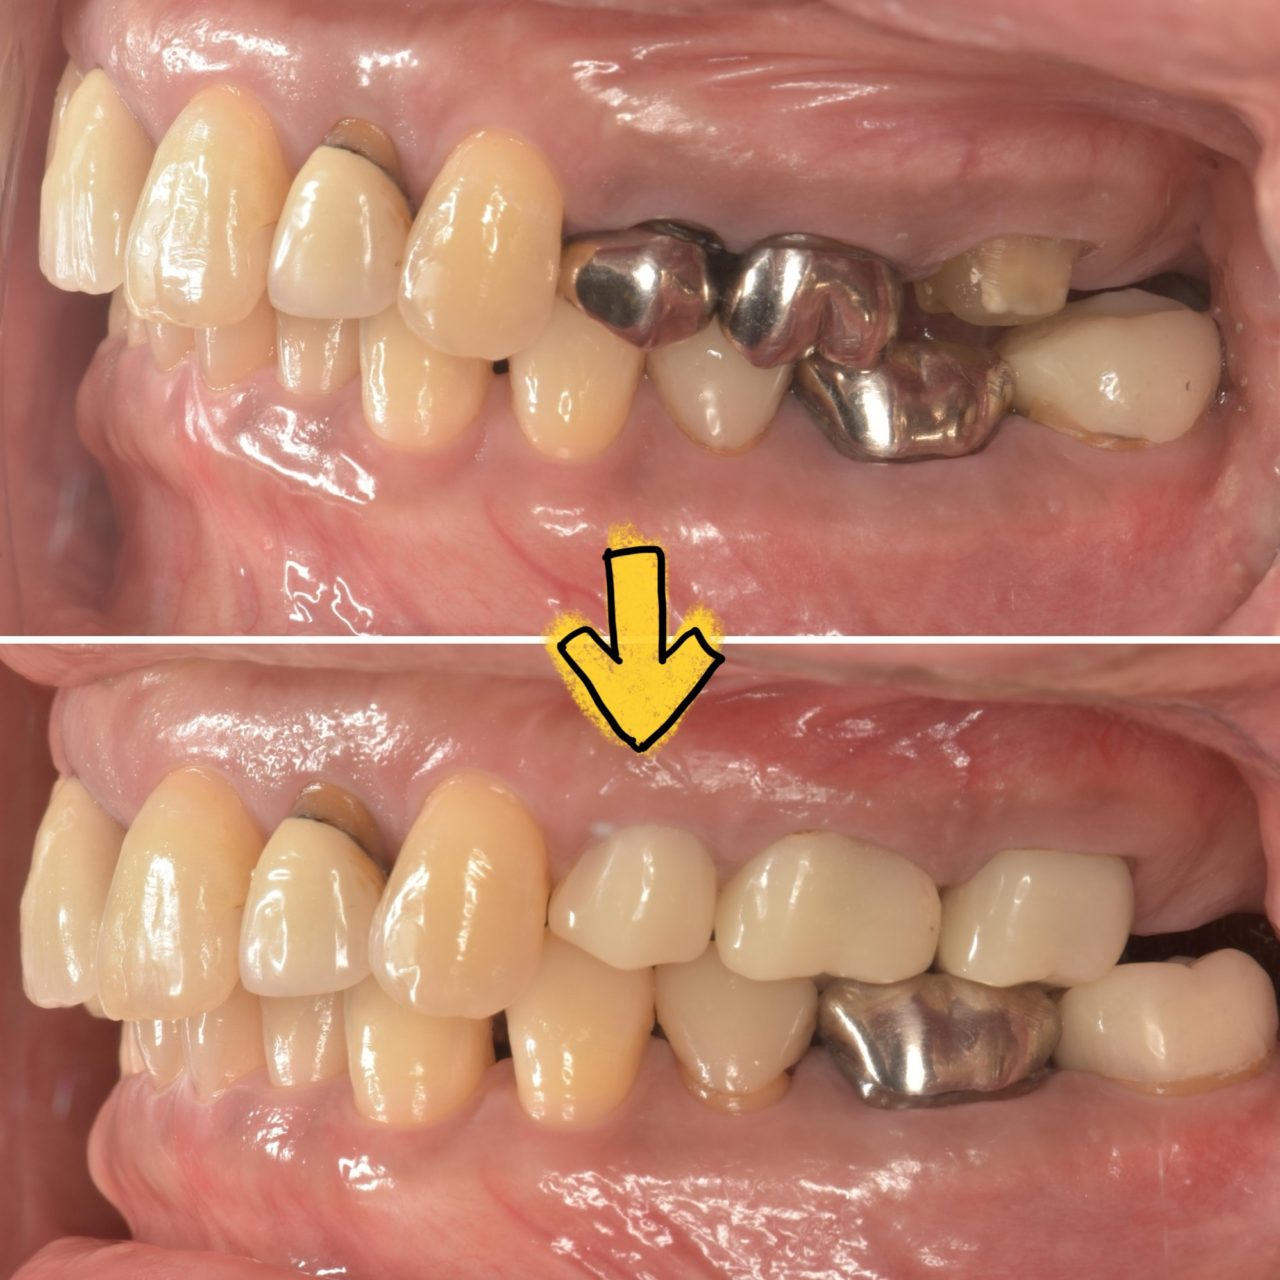

他院で治療を繰り返していた患者様の症例

-

術前

術後

年代/性別 30代/女性 主訴 再発しない治療を受けたい 治療方法 感染根管処置 費用 診断費用:¥16,500

感染根管処置:¥154,000

リトリートメント:¥44,000

ファイバーコア:¥38,500

オールセラミックス:¥187,000

オールセラミックスインレー:¥99,000×3備考 メリット:歯を残す事ができる

他院で治療を繰り返しており “再発しない、よりよい治療を受けたい❞と来院された患者様の症例です。

右上の1番奥の歯に注目して下さい。

銀歯が入っているだけかと思えば、レントゲンで見てみると根の先に黒い影(根尖病変)があるのが分かります。

根尖病変があるということは根管内に感染があり、それが原因で炎症が起きているということになります。 -

CTで見てみると、よりハッキリと分かります。

この後は根管充填と築造(歯の土台を立てること)を行い、仮歯で半年経過観察を行いました。

経過観察の期間を終了し、CTを撮影すると根尖病変がなくなっているのがわかります。 -

経過観察中に、前の歯3本の詰め物もくずれて感染が起きていた為、虫歯治療を行い、部分的なセラミックスを詰めました。

根管治療をした1番奥の歯は、まだ仮歯の為、これからセラミックスに変える予定です。

根管治療後、痛みなどの症状はなく、問題なく食事ができていると報告をもらっています。